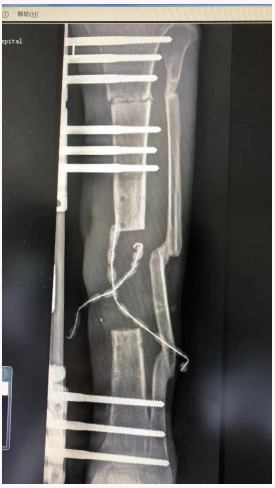

患者X先生,男,31岁,2年前因左侧开放性、粉碎性胫腓骨骨折在江苏宁波某医院住院治疗,充分术前准备后行手术治疗;术后,患者左小腿感染流脓,虽经4次手术,但未见好转,遗留慢性骨髓炎、骨质外露。加之经常有脓液流出,伤口周围皮肤疤痕发黑,每因行走或劳累后患肢疼痛,肿胀加剧,只得扶拐跛行,随后丧失劳动力,被迫返乡,辗转多家医院救治依然无效,伤病严重影响生活,也给其心理带来创伤。

到我院创伤外科住院后,副主任王磊及其团队医护进行详细诊查,针对病因抗炎、换药治疗。期间,王磊带领团队评估伤情、翻阅资料、咨询专家,经多次商议和手术模拟,最终确定手术方案,并实施“搬运手术”。

经术前充分准备,手术过程顺利,术后患者整体情况良好,感染的伤口恢复良好,现骨缺损部分正在逐步生长愈合中。X先生对后续治疗恢复充满信心,笑容逐渐满布脸颊,身体好,心理也好,以后的生活会更好!

骨搬运技术是通过人为方法把骨头切断造成骨折后,在骨折的远近两端安上外固定支架,通过上面的特殊装置,以持续缓慢牵引,向两端延长,延长所产生的空间会通过人体的自然重建功能而生成新骨(称之为牵张成骨)。目前,作为一个被确定的、公认的手术方式,被广泛的应用在各种疾病的治疗中。